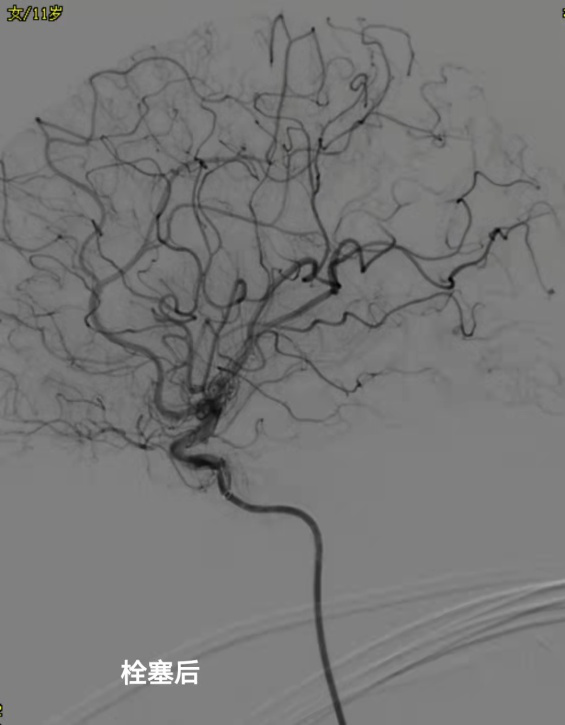

脑科中心三区骆安林主任、吴世强副主任组织科室技术团队作了讨论,认为患者左颞顶部大量血肿,右上肢活动不灵活,已经出现神经功能损害,血肿压迫过久会出现不可逆的功能障碍,情况十分紧急,有急诊手术指征。传统开颅手术创伤大、出血多、恢复时间长,会在小孩身体上留下永久性的手术创伤。经与家属沟通,科室最终结合患者的实际情况,先采用“定向软通道血肿清除术”清除了患者颅内血肿减轻了脑压。随后进一步完善全脑血管造影术检查,发现了患儿脑出血的罪魁祸首——脑动静脉畸形。脑科中心三区遂在我院博士工作站专家、南方医科大学珠江医院脑血管病专家何旭英博士的指导和帮助下顺利为患者施行了“畸形血管栓塞术”,手术效果十分满意,复查造影畸形血管团已不显影,彻底解决了患者的后顾之忧。最后,患者完全康复出院,没有留下任何后遗症。